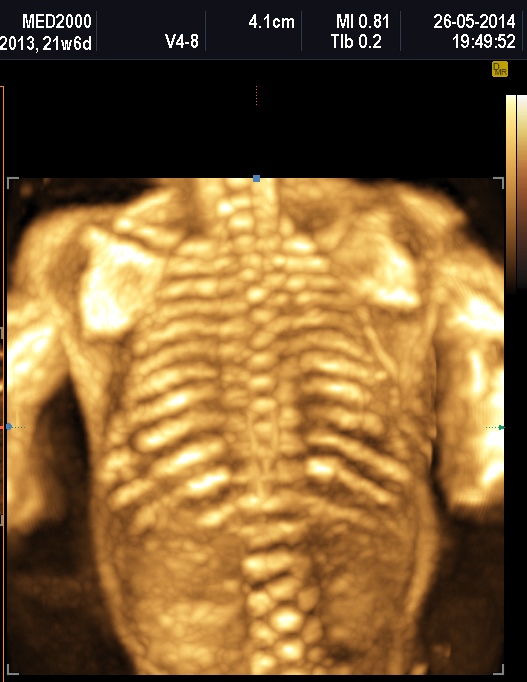

Per quanto riguarda il rachide la Platispondilia (comunque non facilmente evidenziabile ecograficamente) è presente nella Displasia Tanatofora e nella Displasia Metatropica. Nell'Acondrogenesi tipo I si ha scarsa ossificazione dei corpi vertebrali e costantemente non si visualizza il sacro.

La misura della circonferenza toracica con un valore < 5° percentile è un indice di ipoplasia polmonare, causa di distress respiratorio nel neonato e indice di letalità. La biometria toracica e la morfologia toracica possono orientarci verso una particolare forma di displasia: se il torace è eccessivamente piccolo potrebbe trattarsi di una Displasia Tanatofora; se il torace è lungo e stretto potrebbe trattarsi di una Sindrome di Jeune; se le coste sono molto corte potrebbe trattarsi di una Sindrome coste corte con o senza polidattilia; se ci sono fratture costali potrebbe trattarsi di una Osteogenesi Imperfetta tipo II; se le coste sono fuse tra loro potrebbe trattarsi di una Displasia Spondilocostale.